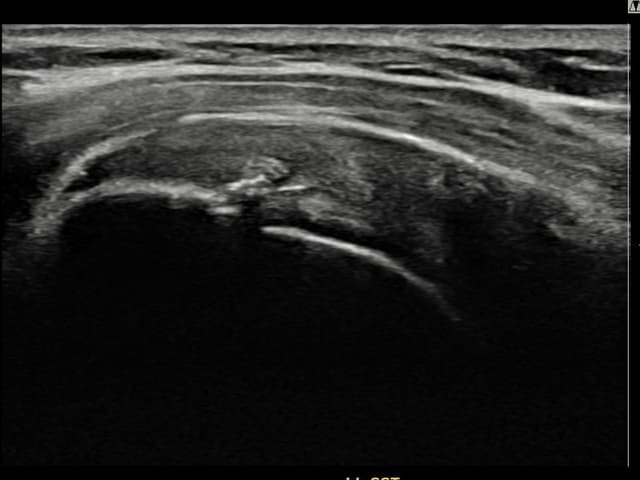

[経過期間: 23.09.01~23.11.03]

[縫縮術] 超音波検査にて右 棘上筋腱 滑液包面側部分断裂(8mm × 4mm (腱厚の約35%欠損))を確認。縫縮術施行後、腱の連続性が回復し、日常生活に復帰されました。